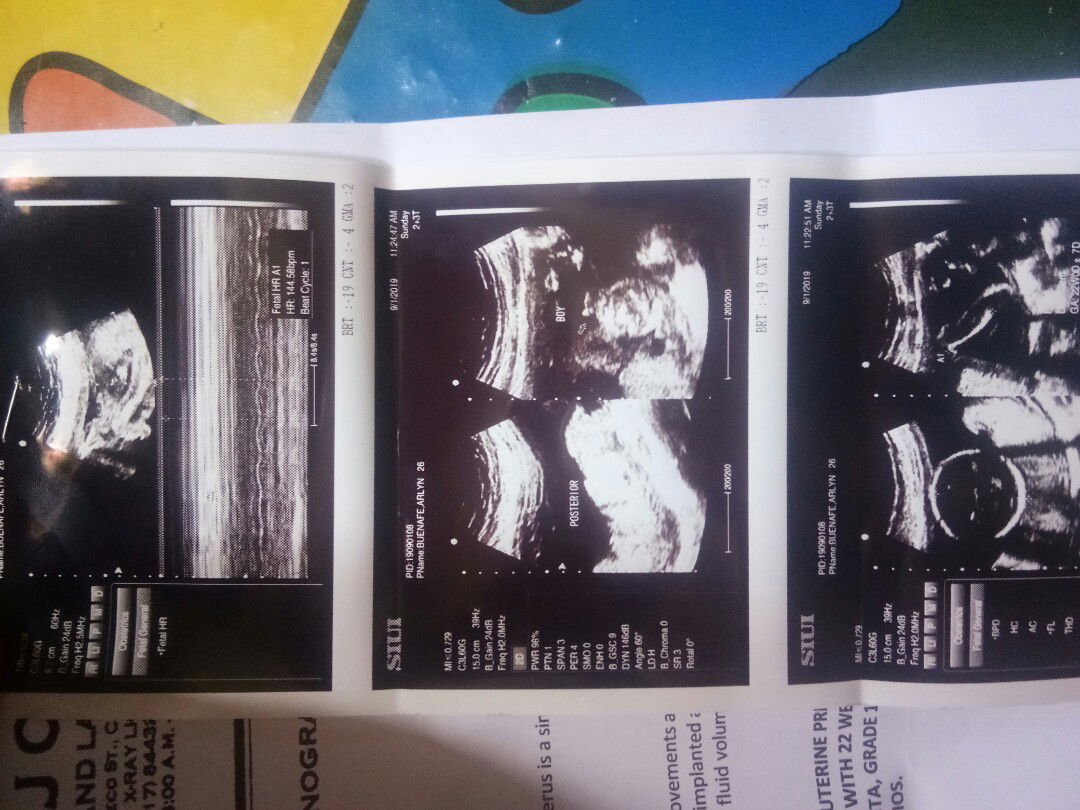

Flex ko lang po baby ko. Its a baby boy, kahit 22 wiks and 2 days palang sya nakita na agd gender nya. Im happy kase one girl and one boy na anak ko.. Kayo mga mommy ilang wiks bago nkita?? Pasalamat po ako kase kahit mtaba ako nkita agd sya, ndi sya mabalutan ng taba. Hehehe